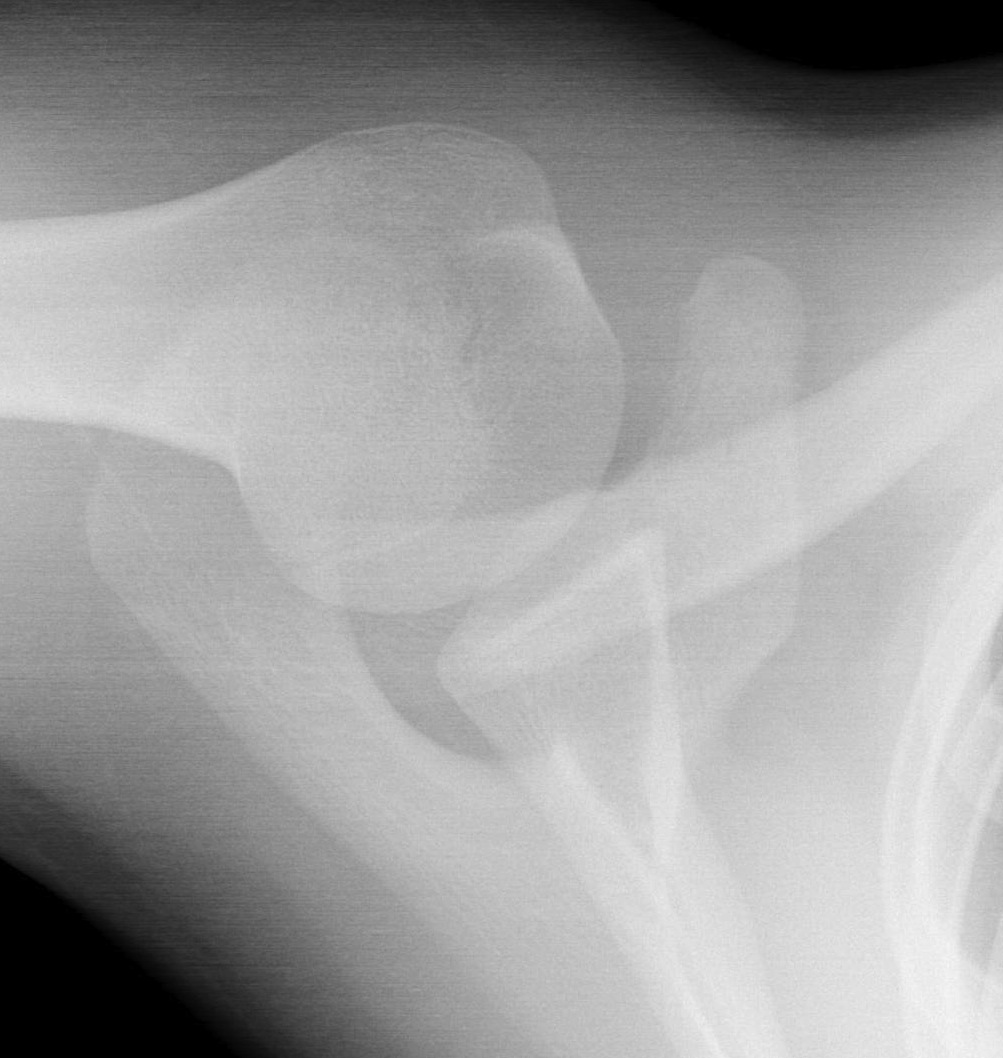

VI Subcoracoid dislocation

Type VI / Subcoracoid dislocation

Rare / can be missed

Risk of neurovascular injury / high velocity injury / associated with multi-traumas

Requires open reduction and fixation

- will have to release soft tissue off coracoid if not already avulsed

- i.e. pectoralis minor / coracoacromial ligament

- attempt to reduce with lateral traction of arm

- may need to release conjoint / perform coracoid osteotomy

- stabilize as needed

Subcoracoid dislocation case report